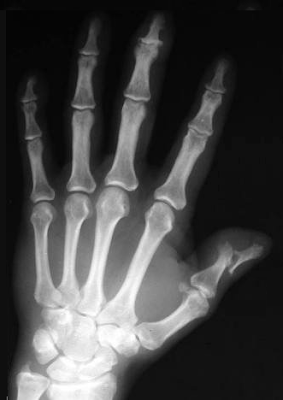

Radiographie antéro-postérieure de la main gauche d'un sujet atteint de rhumatisme psoriasique. Notez l'atteinte inflammatoire-érosive des articulations du premier doigt et l'atteinte initiale de l'interphalangienne distale du troisième doigt

Source iconographique et légendaire : https://it.wikipedia.org/wiki/Artrite_psoriasica